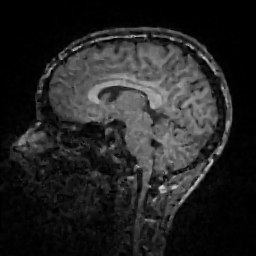

Improving image reconstruction from a sparse set of known pixels was the main motivation behind our work. Therefore, we applied it to two well-known natural images, lena and peppers, as well as to a medical image, a slice of a weighted brain MR scan (t1slice). For lena, we kept a random subset of only of the pixels. Due to the lower resolution of the peppers and t1slice images, we kept and , respectively.

Results for lena are shown in Figure 2, for peppers in Figure 3, and for t1slice in Figure 4. A quantitative evaluation in terms of MSE and AAE is presented in Table 4.1. In terms of the numerical results, our proposed method produced a more accurate reconstruction than any of the competing approaches. Visually, there is a clear difference between second-order (EED) and fourth-order approaches (Li1, Li2, FOEED). Especially, we found that the shapes of edges were reconstructed more accurately. For example, we noticed this around the shoulder and hat in the lena image (Figure 2). Similarly, the white and grey matter boundaries were better separated in the t1slice (Figure 4).